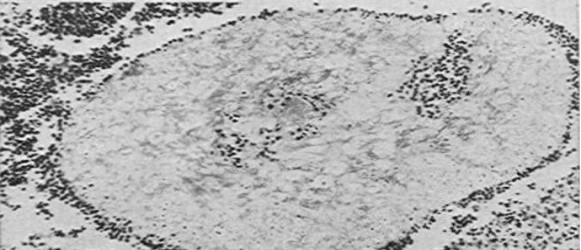

The clinical picture of mycetoma due to aspergilli is not different from that caused by eumycetoma due to known fungi. It occurs on the foot in most cases (Figs.1 & 2) and other sites as in the American case [9]. However there were two unusual phenoma in the Sudanese cases. The lesion caused by  A.nidulans showed  more bleeding than usually seen in mycetoma and that caused by A.flavus was more painful than what usually reported by mycetoma patients.

Figure1: Mycetoma of the right foot due to A.nidulans.

Figure2: Mycetoma of the right foot due to A.flavus.